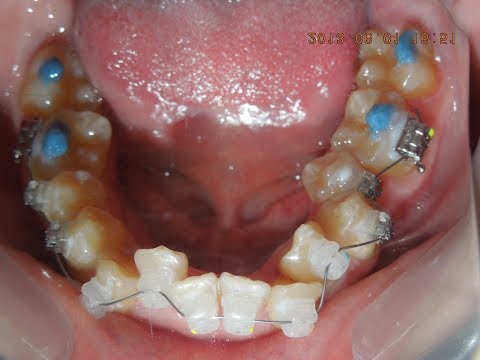

下の奥歯が内側に倒れ、咬み合わせの高さが低い。

そのままでは、奥歯に矯正装置も着けられない。

バイトターボ(青や白のレジン)を使い、咬み合わせを挙上し、

そのすきに、前歯を並べてしまう。

そのあと、徐々に奥歯の立て直し。